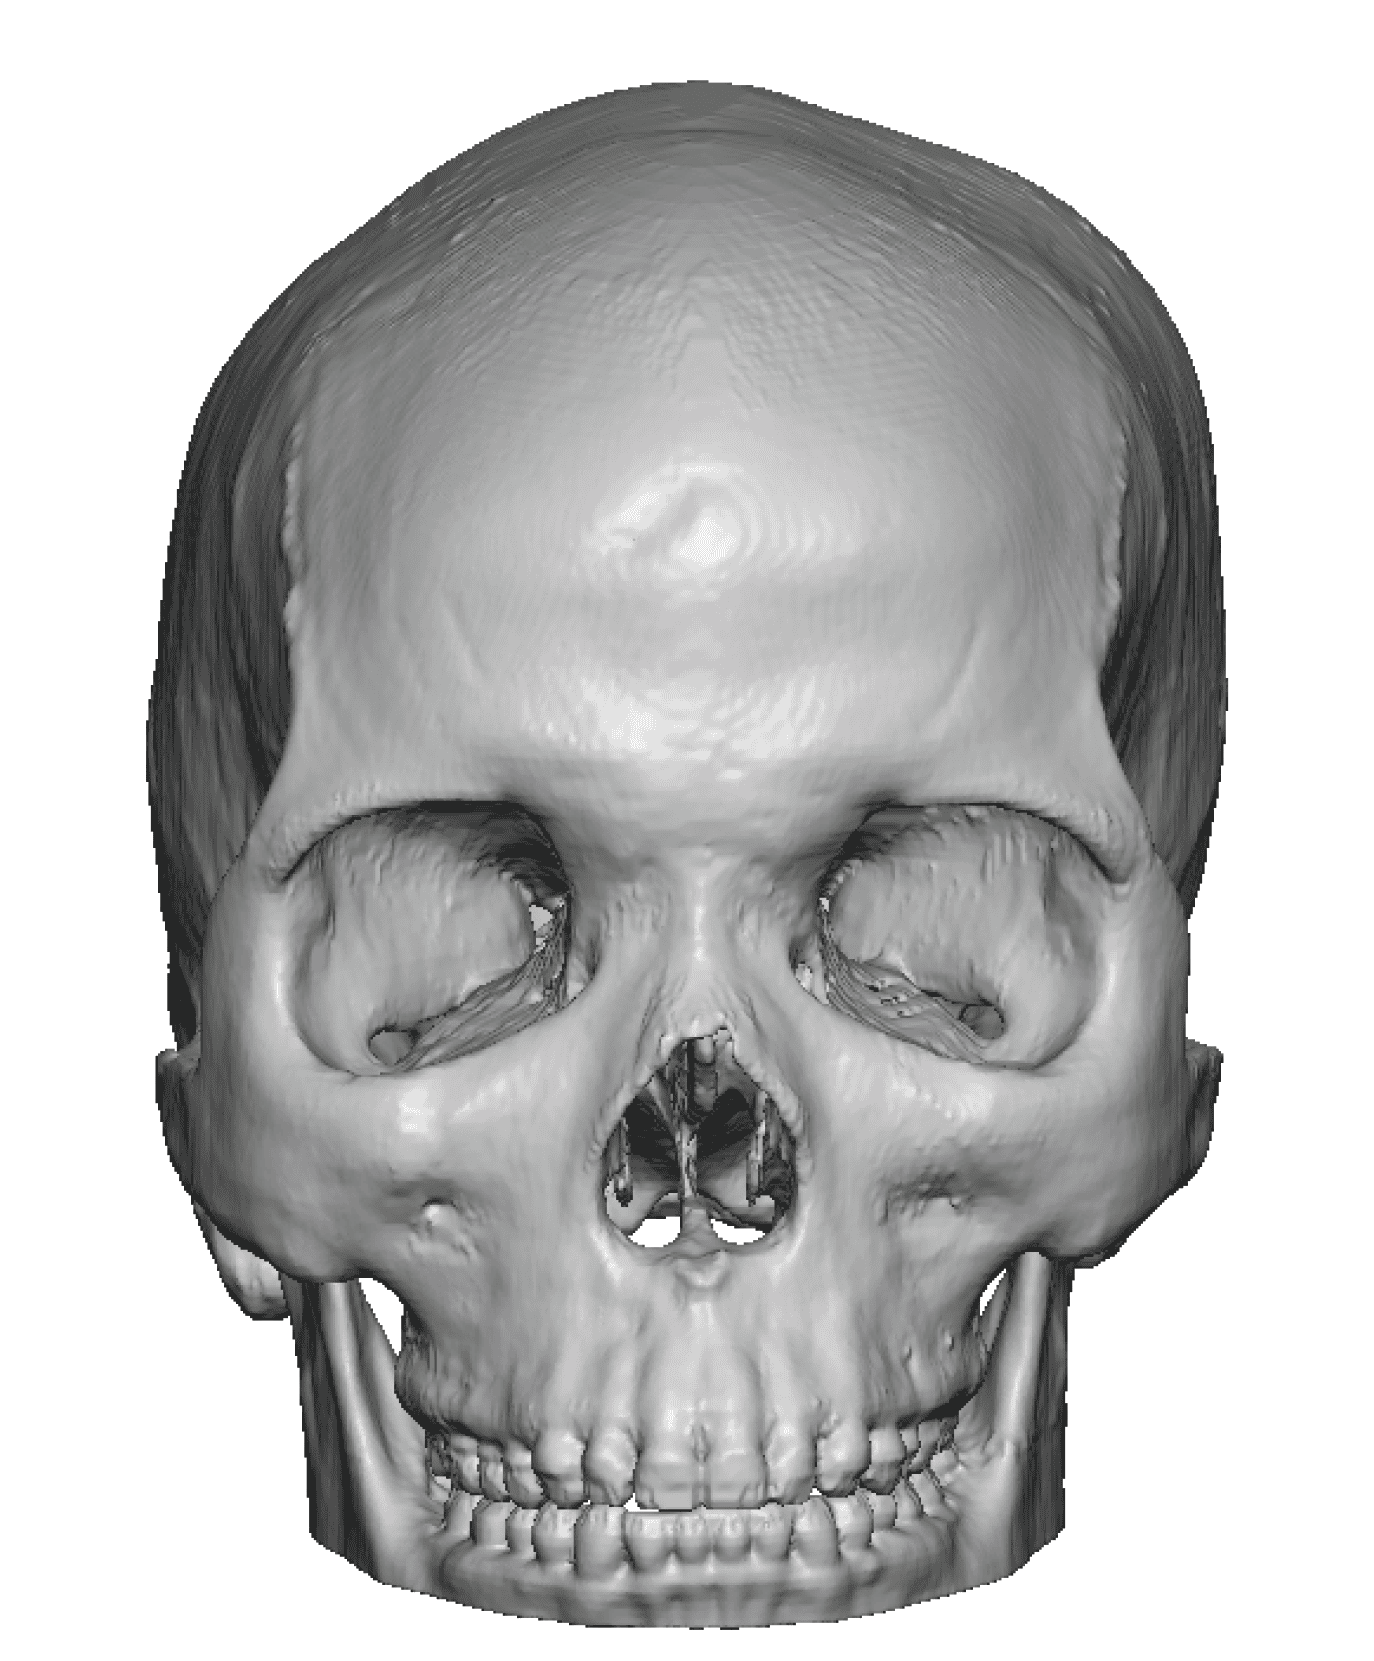

Severe narrowing skull deformity from prior sagittal craniosynostosis repair as an adult.

Complete replacement of entire skull by a custom implant with temporal fat injections.

Severe narrowing skull deformity from prior sagittal craniosynostosis repair as an adult.

Complete replacement of entire skull by a custom implant with temporal fat injections.